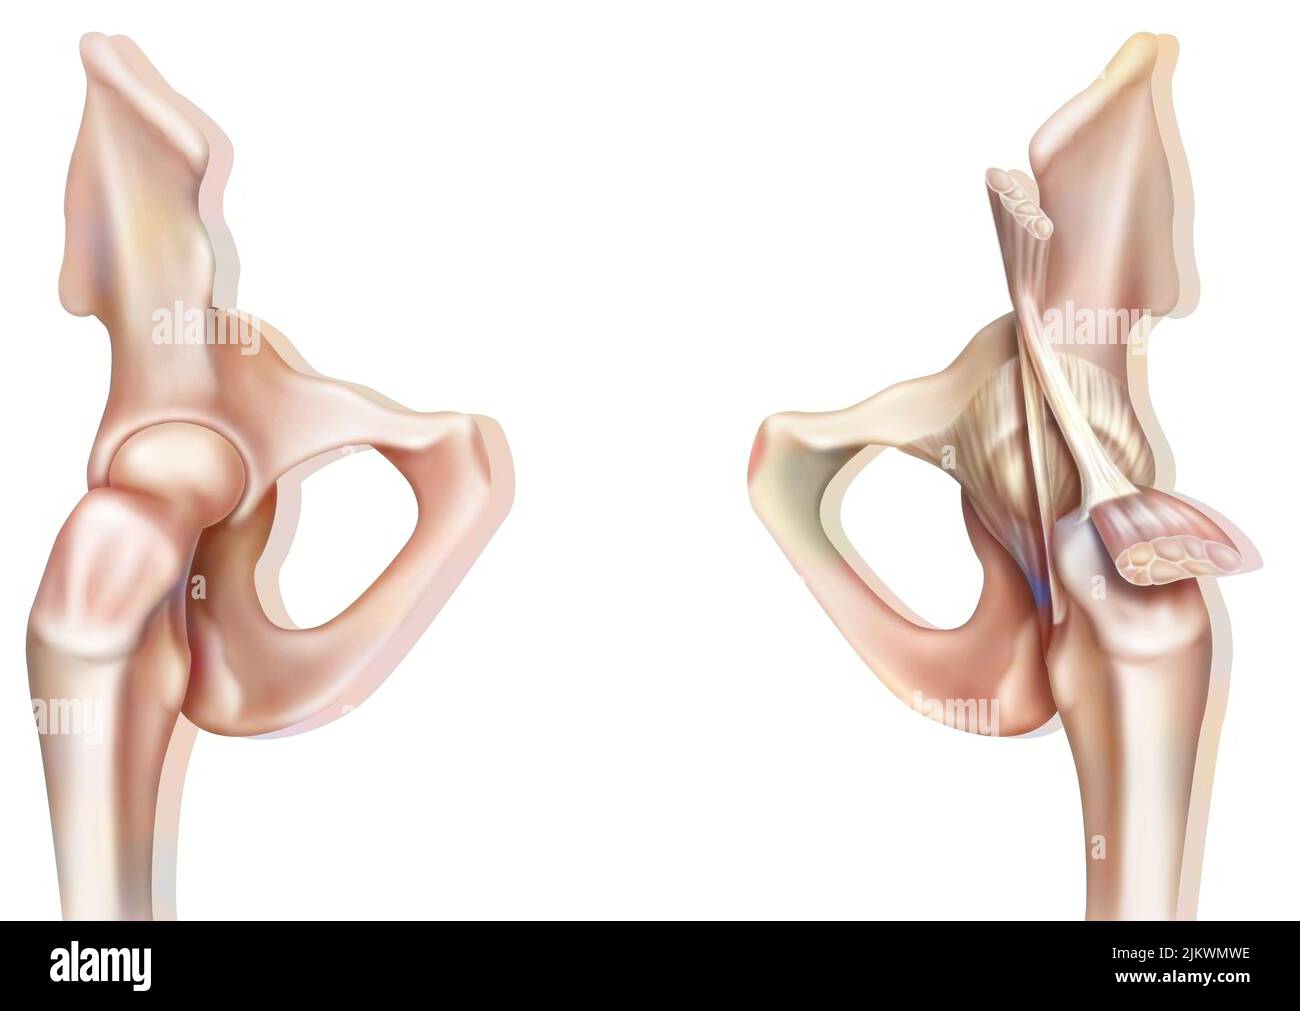

Bone joint of the hip without and with the coxofemoral joint capsule. Stock Photohttps://www.alamy.com/image-license-details/?v=1https://www.alamy.com/bone-joint-of-the-hip-without-and-with-the-coxofemoral-joint-capsule-image476923594.html

Bone joint of the hip without and with the coxofemoral joint capsule. Stock Photohttps://www.alamy.com/image-license-details/?v=1https://www.alamy.com/bone-joint-of-the-hip-without-and-with-the-coxofemoral-joint-capsule-image476923594.htmlRF2JKWMWE–Bone joint of the hip without and with the coxofemoral joint capsule.